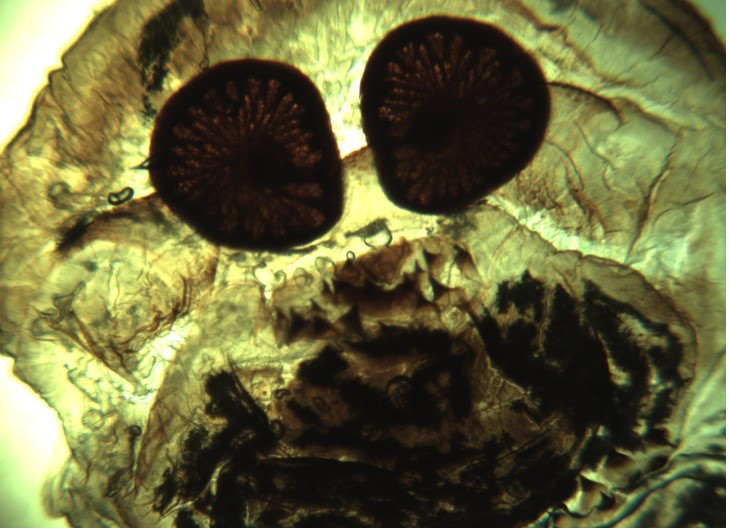

Figure 3

Cross section of rostral part of O. ovis larva (under 4x microscopy)